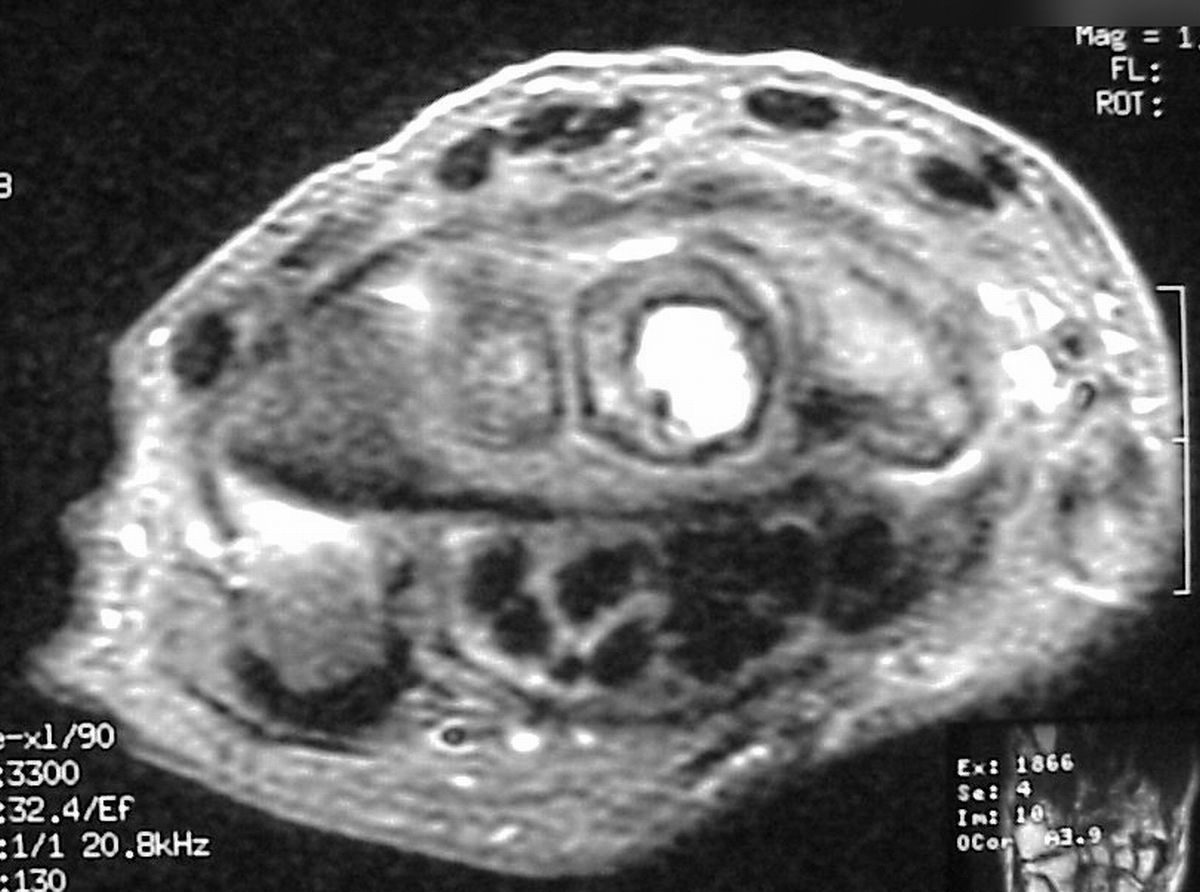

| Pathology:

decalcified specimen showed empty spaces, hemorrhage,

stromal elements and multinuclear osteoclasts - not to

be confused with giant cells. |

| Microscopic

pathology similar to the prior case, confirming the

diagnosis of aneurysmal bone cyst. |